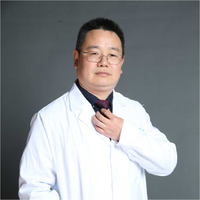

我们先来看2022年3月主要病灶的影像:

右上叶结节实性,密度高,边缘平整,轮廓清楚,像良性些。